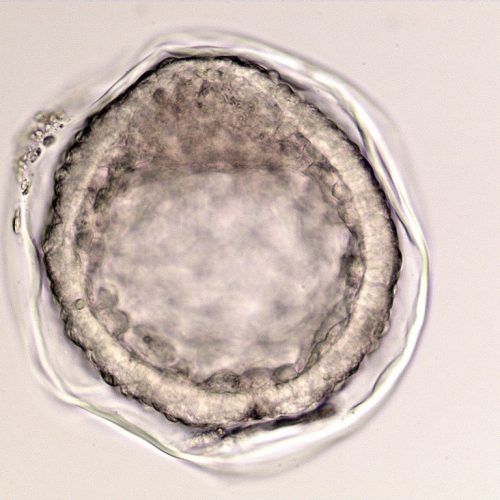

- Capsule: The embryonic capsule is unique among domestic mammals. This is a glycoprotein protective coat formed by the trophoblast layer beneath the zona pellucida. It forms only after the embryo enters the uterus, so embryos grown in a laboratory do not develop the capsule until after they are transferred. If not protected by either the zona pellucida or the embryo capsule, an embryo cannot survive in the uterus.

- Growth rate: Once the embryo becomes a blastocyst and starts expanding around day seven, the embryo will nearly double in size each day until day 12. This allows early ultrasound determination of pregnancy status, as an embryo around 300-400 microns (0.3-0.4mm) in size when recovered at day seven will grow to 3-4mm, large enough to be visualized on an ultrasound scan, by day 11.